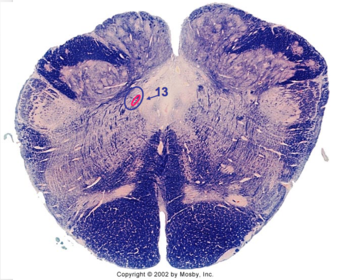

| Nucleus gracilis | |

| Nucleus cuneatus | |

| Fasciculus gracilis | |

| Fasciculus cuneatus | |

| Internal acruate fibers | |

| Lateral (external/accessory) cuneate nucleus | |

| Medullary pyramids | |

| Hypoglossal nucleus | |

| Hypoglossal nerve | |

| Dorsal motor nucleus of X | |

| Nucleus ambiguus | |

| Solitary tract | |

| Solitary nucleus | |

| ALS | |

| Medial lemniscus | |

| Medial longitudinal fasciculus | |

| Spinal tract of V | |

| Spinal nucleus of V | |

| Lateral (external, accessory) cuneate nucleus | |

| Anterior spinocerebellar tract | |

| CN IX | |

| Inferior cerebellar peduncle | |

| Inferior olivary complex | |